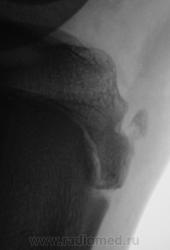

Пациент направлен на рентгенографию коленного сустава с диагнозом - Болезнь Осгут - Шлаттера.

фрагментация бугристости Б\Б кости

Трактовать надо так: до 18 лет это-остеохондопотия; после 18лет это асептический некроз.

А может "норма"? А может вариант развития бугристости?

Болезнь Осгут - Шлаттера, как-то не вдохновляет. Более склонен к консоидирующемуся отрывному перелому бугристости б/берцовой кости.

Более склонен к варианту окостенения, хотя травматический генез, как и асептический некроз (абсолютно согласен с Максималистом - при наличии клиники и анамнеза) с повестки дня окончательно, до выяснения оных, не снимаются.

Уважаемые коллеги! На мой взгляд, выявленное на рентгенограмме, образование костной плотности, с четкими, ровными контурами, однородное по своей структуре отношения с бугристости большеберцовой кости не имеет. Хотелось бы знать возраст пациента, его анамнез (спорт, травмы области коленного сустава). Больше похоже на обызвествления собственной связки надколенника. Дополнил бы УЗИ коленного сустава.

16 лет "учтенному лицу", ранее жалоб не было, рядом "мама", которой доктора посоветовали..., вот и вся история...